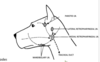

Label the green and purple area

Label the coloured part of this photo

List the 3 compartments of the frontal sinus

rostal

medial

Lateral extend to the front process